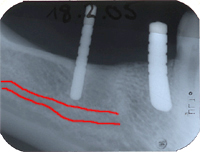

- Auf den Röntgenbildern von Abb. 3 und 4 sieht man den Verlauf eines sensiblen Nerves im Unterkiefer-Knochen (rot hervorgehoben). Dieser Nerv versorgt unter anderem die Unterkiefer-Lippe sensibel und darf bei der Implantation nie verletzt werden. Um dieses Ziel zu erreichen, wird vor jeder Implantation im Unterkiefer-Seitenzahngebiet ein Röntgenbild mit einer Metallkugel von 5 mm Durchmesser gemacht, um die Höhe des Knochens bis zu diesem Nerv in etwa zu berechnen (Abb 3).

In diesem Fall wurde der bis auf den Knochen abgefaulte eigene Zahn rechts der im Röntgenbild weissen Metallkugel gezogen (Abb. 3). Die absolute, genaue Berechnung der Höhe des Knochens bis zu diesem Nerv erfolgt während der Operation mit sogenannten Tiefenmesslehren (Abb. 4). Damit ist es mir möglich, das längenmässig richtige Implantat optimal in den Knochen und ohne Risiko einer Verletzung für den Nerv zu setzen (Abb. 5).